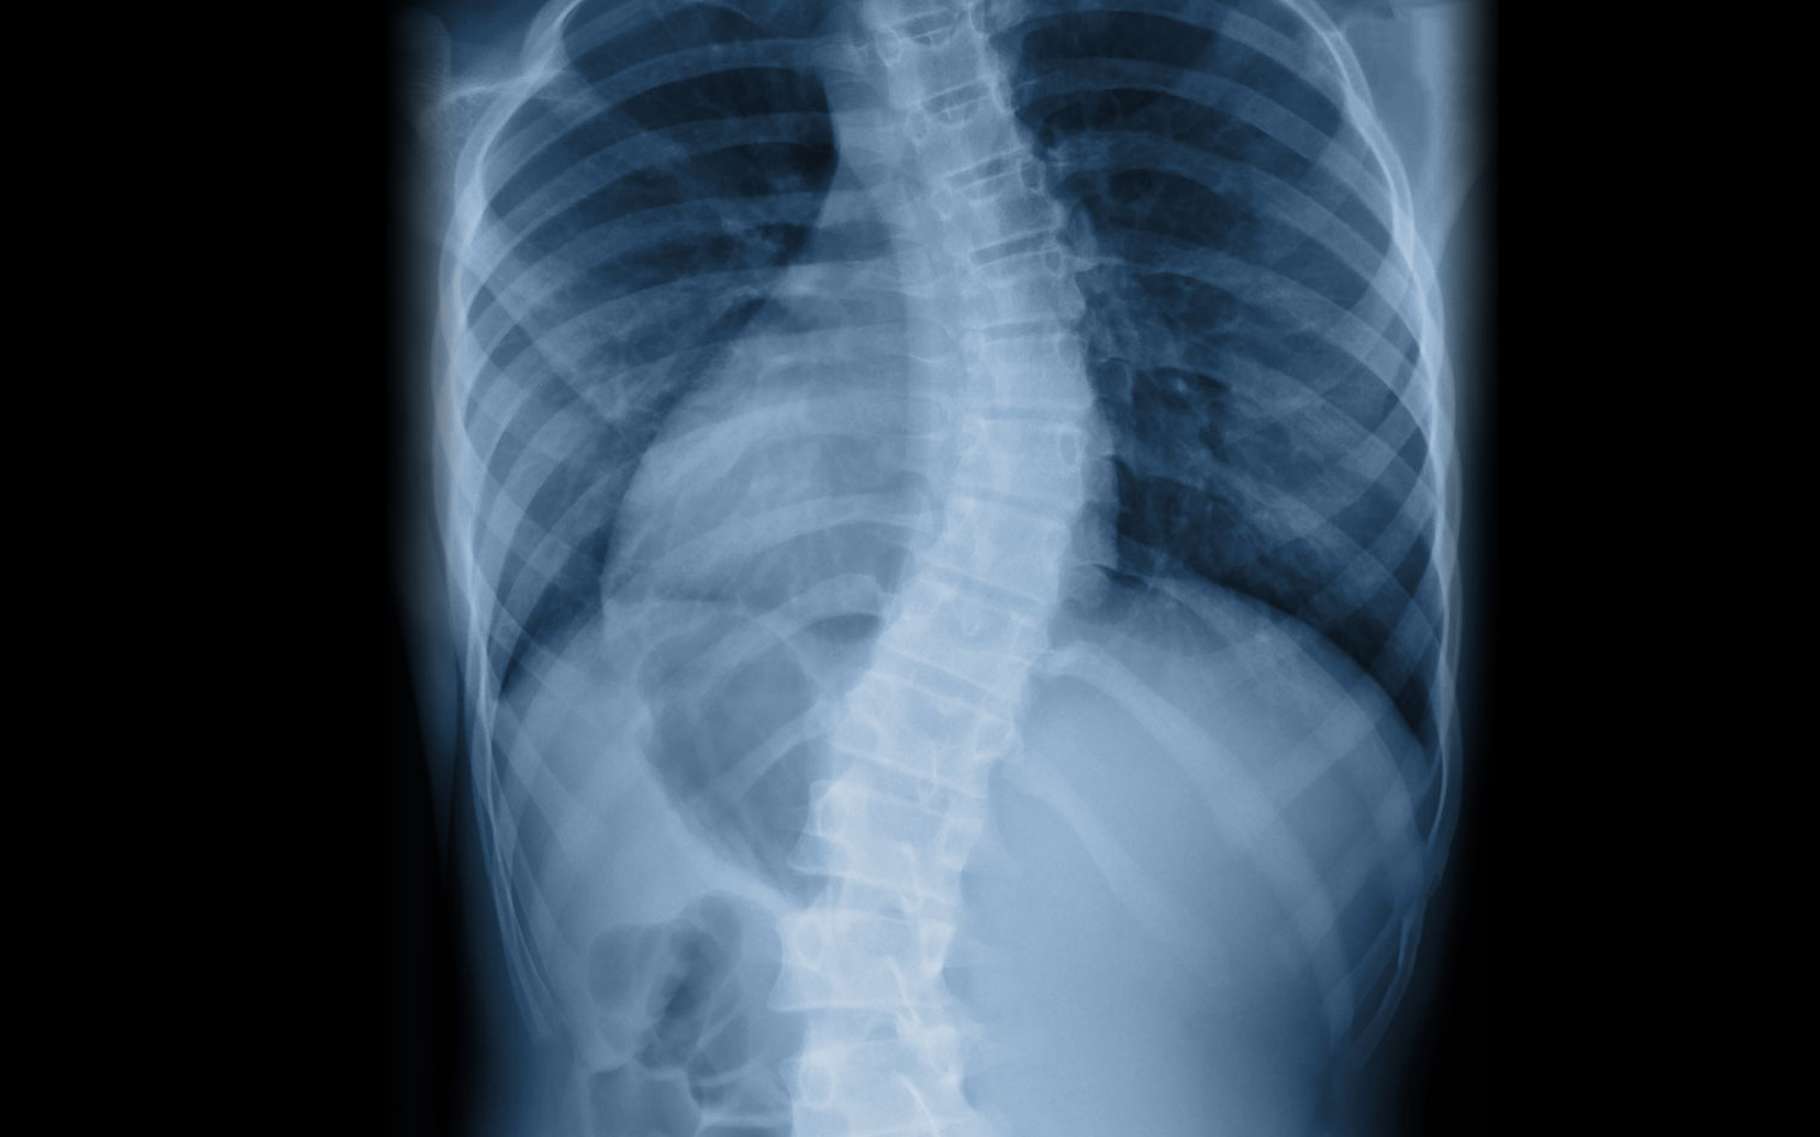

Scoliose et cyphose les principales déformations rachidiennes

Déformations Rachidiennes (scoliose, cyphose) Institut Parisien du Dos

Colonne vertébrale Cyphose Hypercyphose Hypocyphose Thoracique